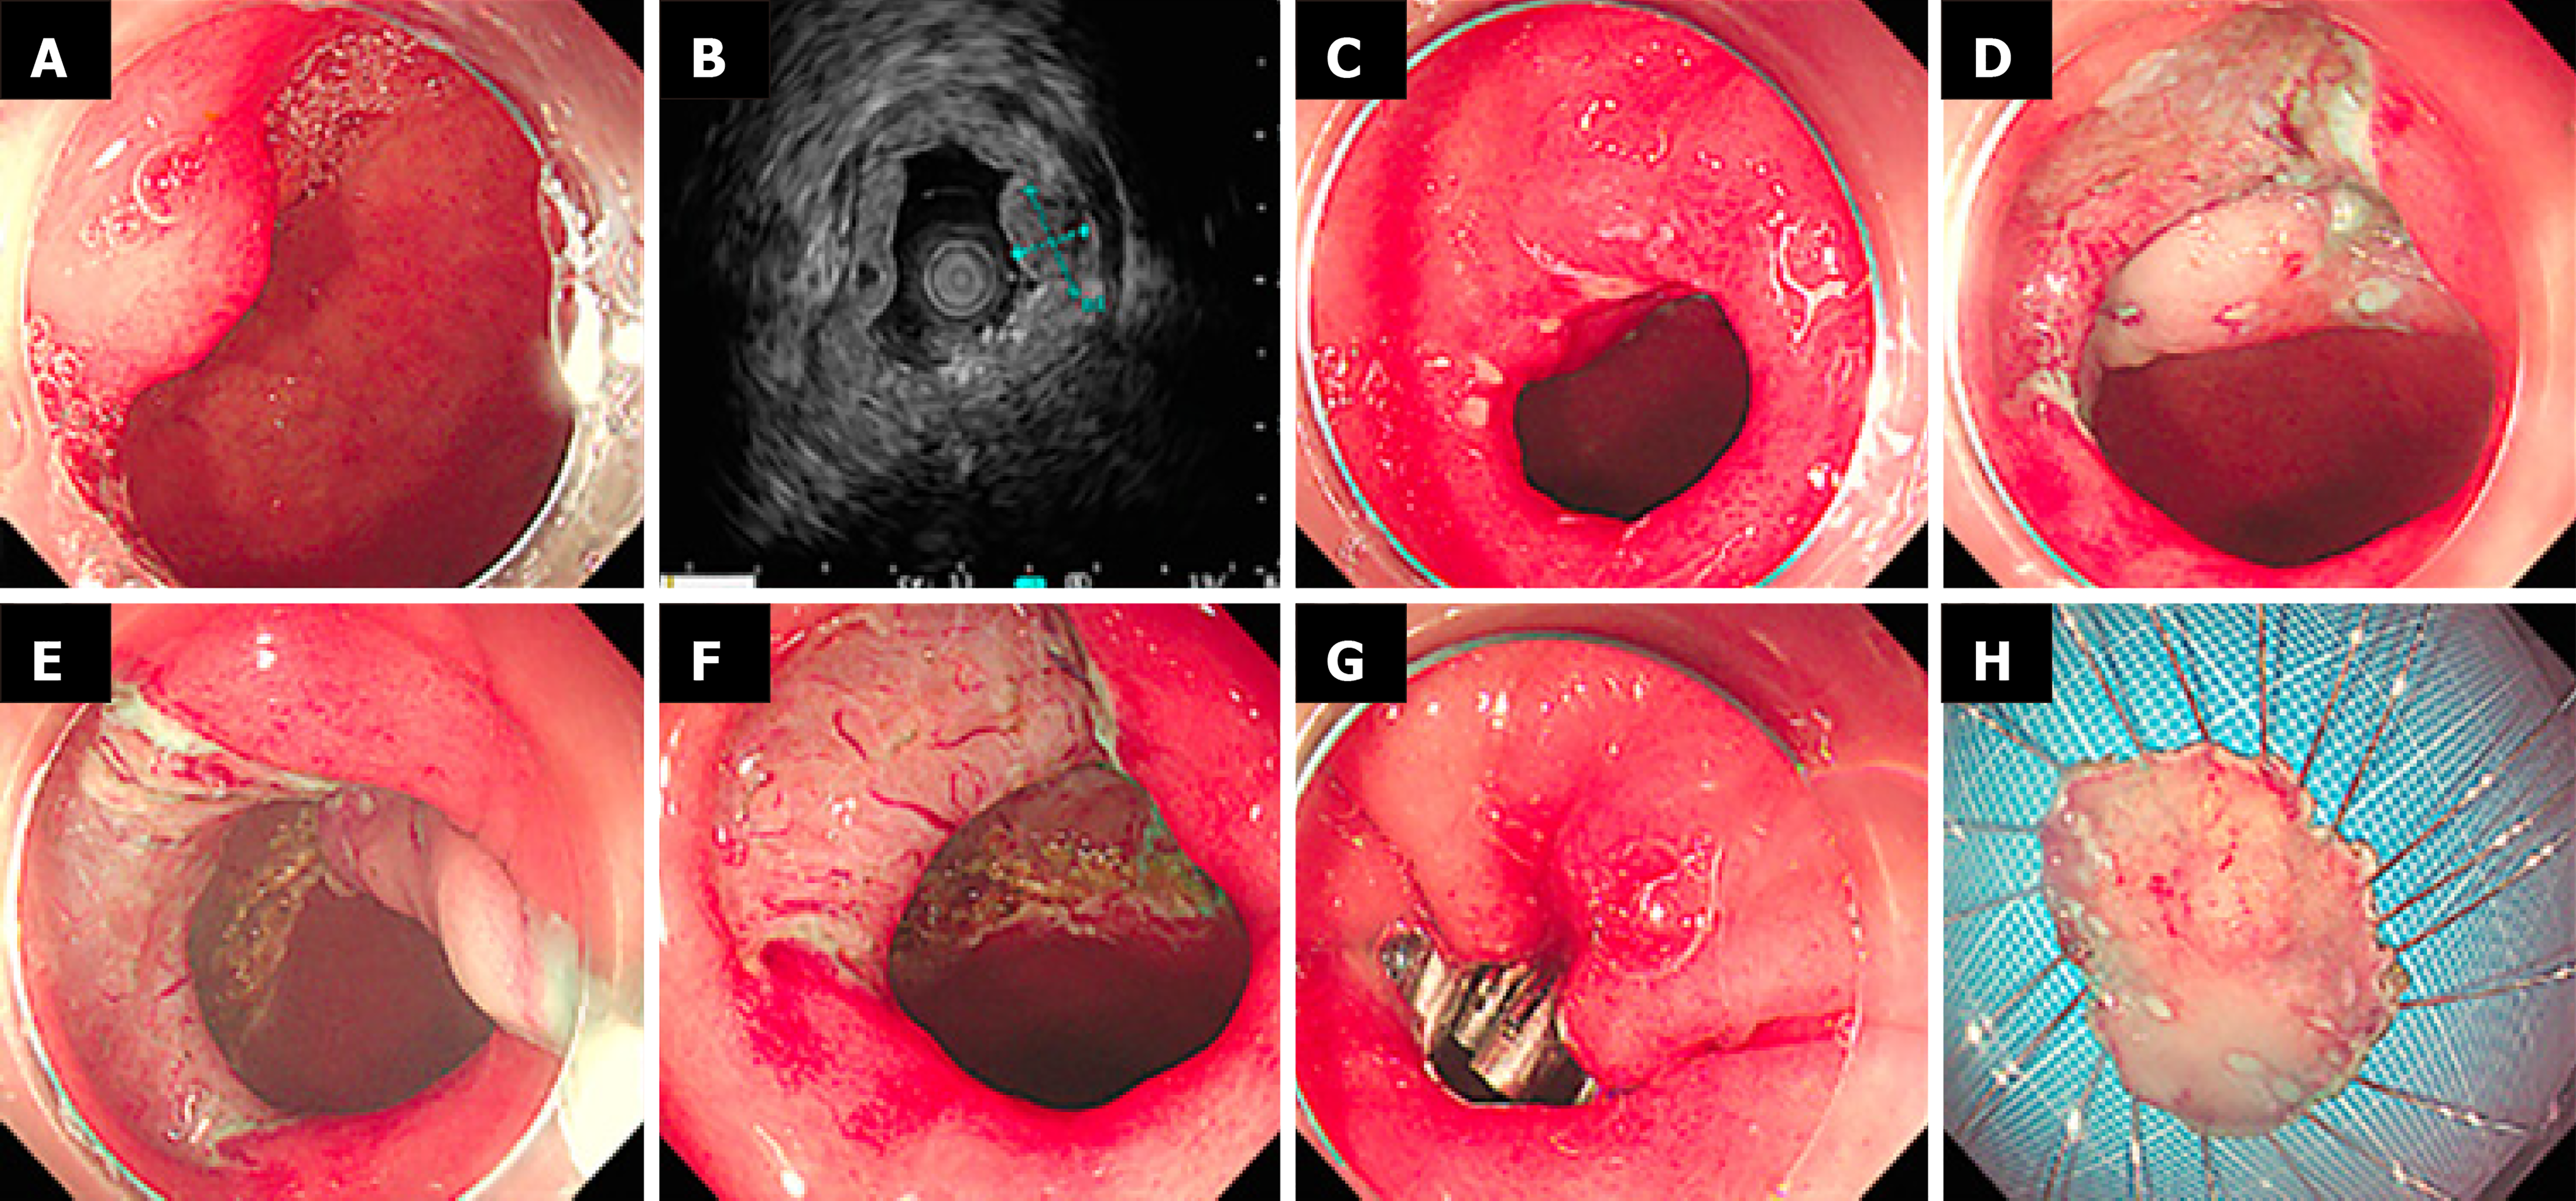

Figure 3 Endoscopic submucosal dissection for sporadic nonampullary duodenal tumor.

Submucosal tumor, 10 mm × 6 mm, neuroendocrine tumor G1, vertical margin (-), horizontal margin (-). A: Lesion in the bulb; B: Micro-probe endoscopic ultrasonography showed a hypoechoic lesion in the second layer; C: Marking; D and E: Dissection with golden knife; F: Post-endoscopic submucosal dissection ulcer; G: Clip closure; H: En bloc specimen.